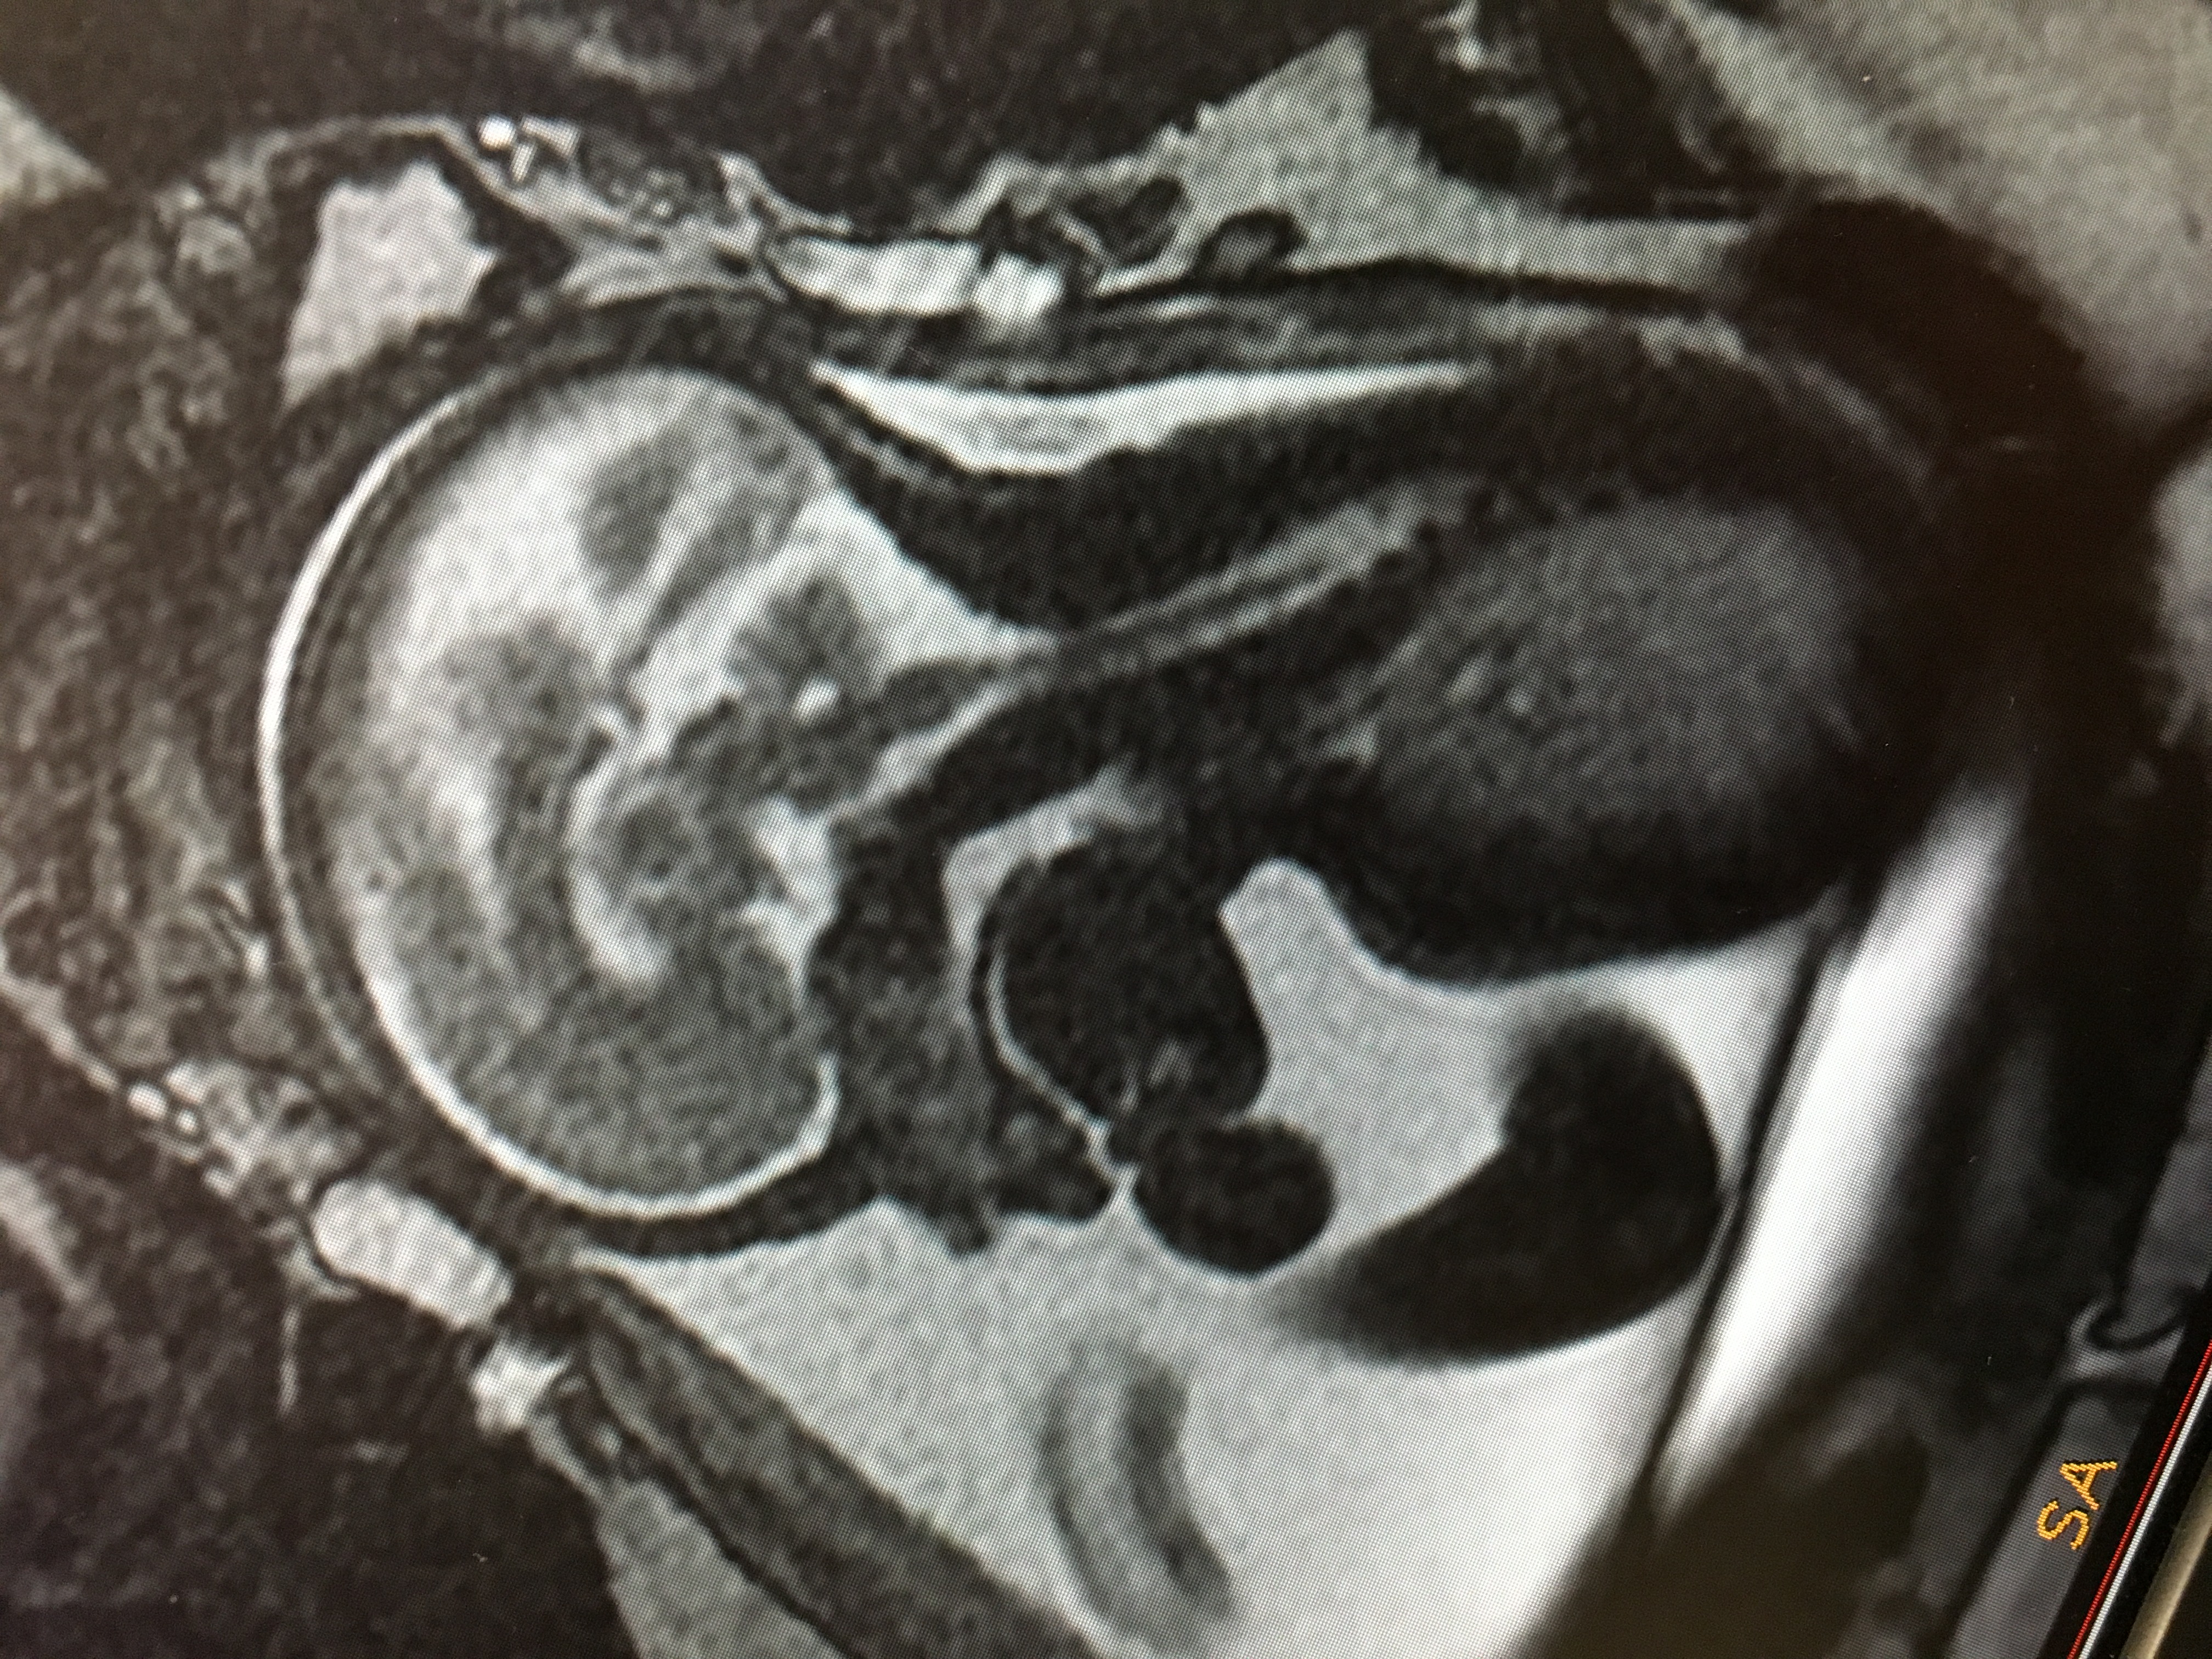

• I don't know if the video will work, but as part of a medical trial which we volunteered for, we had an MRI scan on our baby, the photographs and videos we got to see of him are truly amazing!

They are still looking for volunteers within the UK who are around the Sheffield area so I don't know if anyone else would be interested just PM me :smiley: